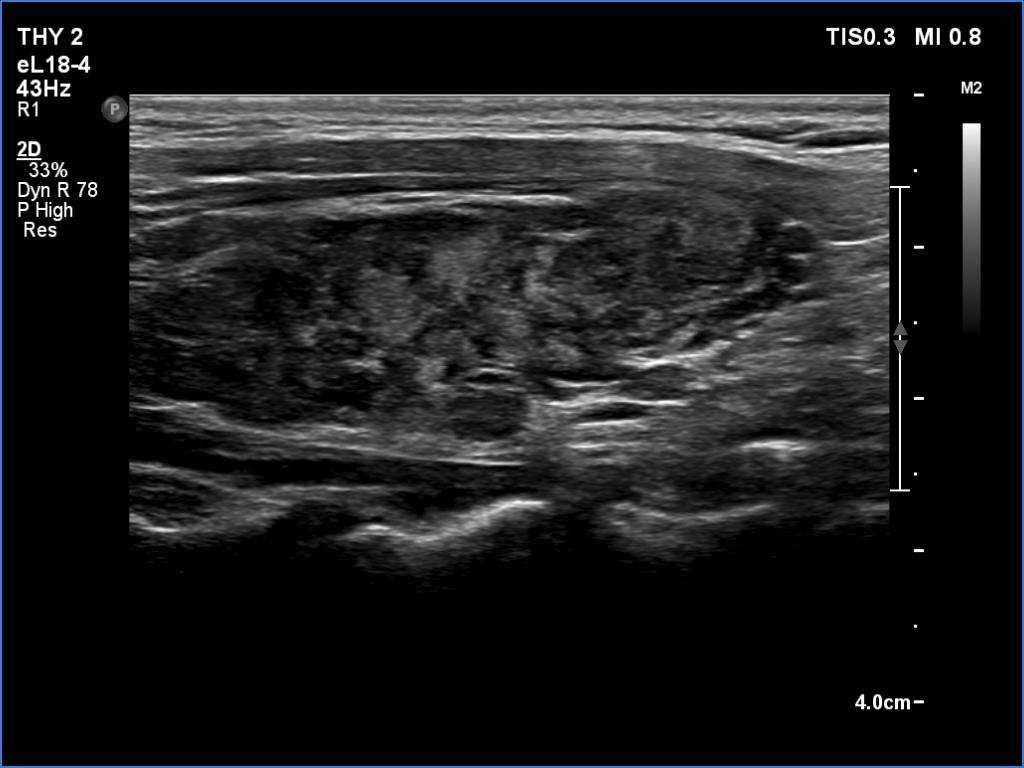

Ultrasonography. The thyroid was deeply hypoechoic and had numerous discrete iso/hyperechoic lesions. The latter had irregular shape and borders. The vascularity was increased. None of the discrete lesions corresponded to pathological nodules.